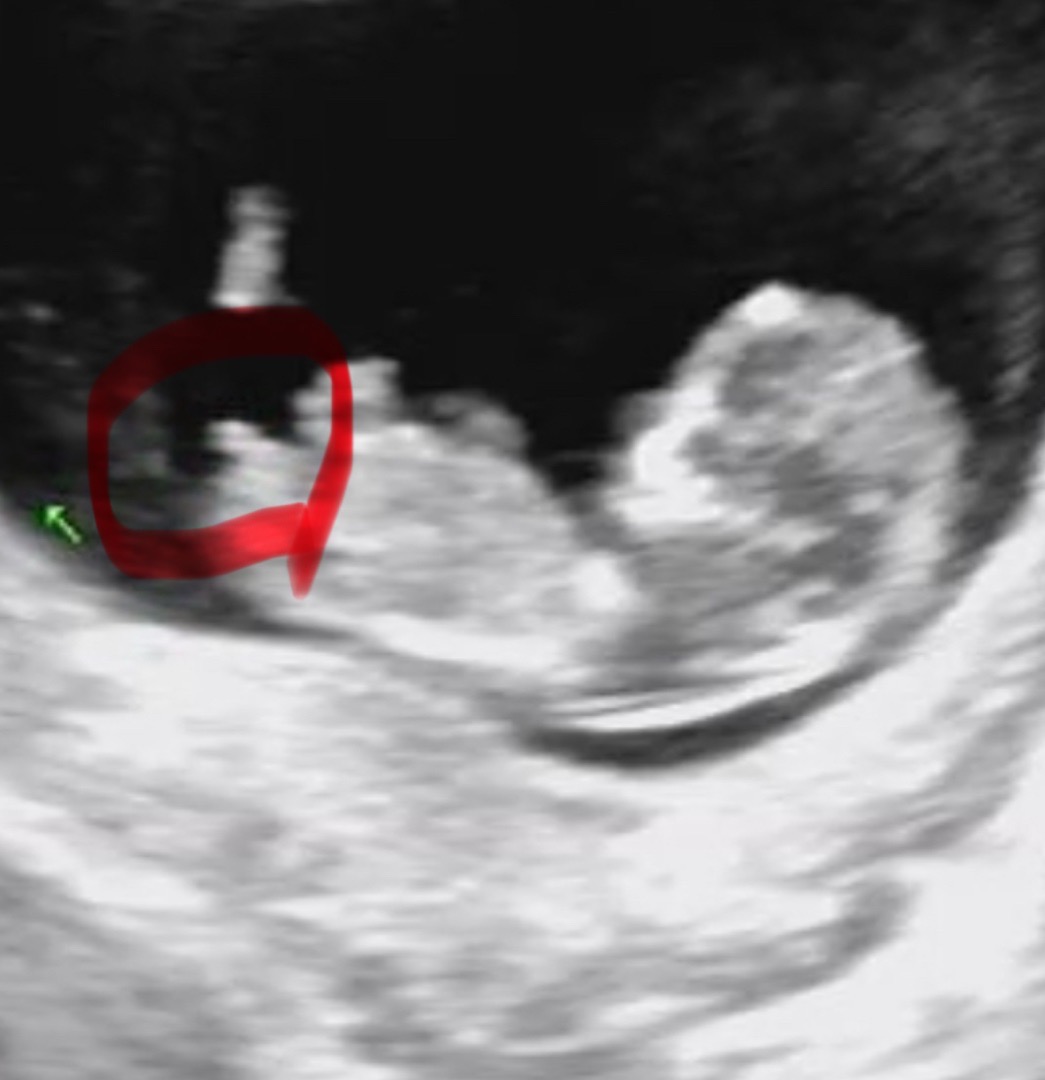

정말 ㅋㅋㅋ너무 봐드리고싶은데 촘파 사진이 ㅠㅠㅠㅠ 각도가 다 제대로 다 안나왔어요...🥹🥹🥹각도 제대로 해서 올려주시면 ㅋㅋㅋㅋㅋ 열심히 봐드릴게요!!!!🥹🥹 동그라미 친 부분이 나와야해요!!